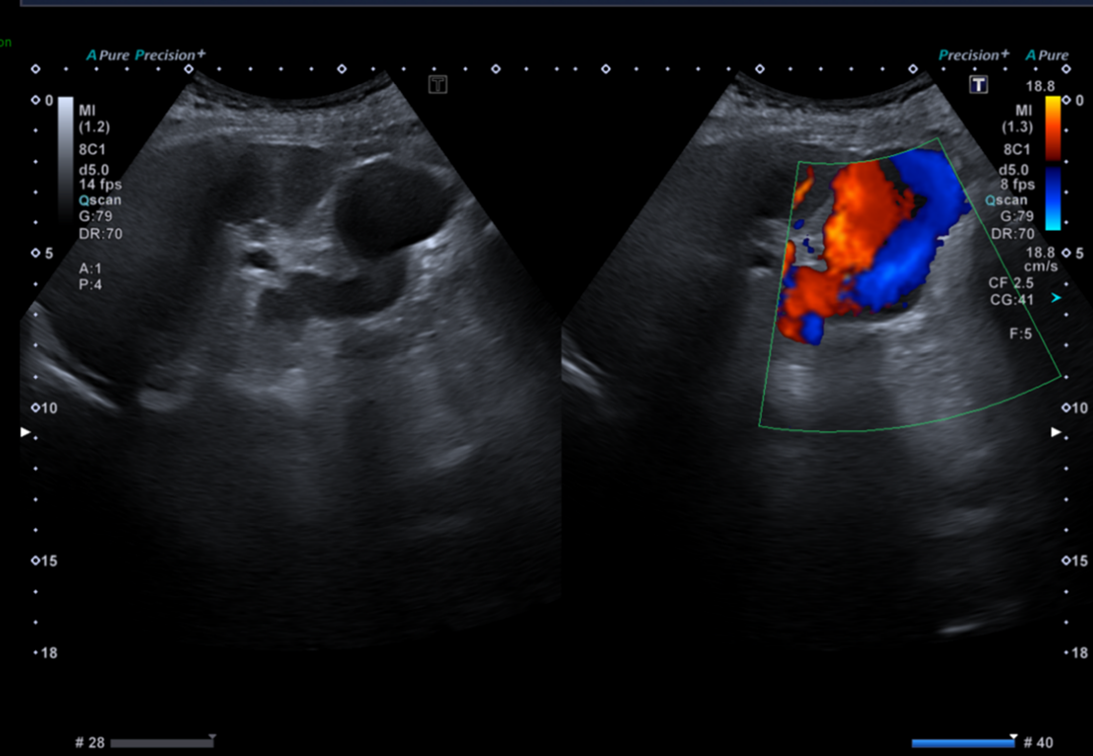

Pour illustrer cela, à quoi vous fait penser cette formation anéchogène située au pôle inférieur du rein gauche sur cette coupe d’échographie abdominale réalisée dans un contexte de surveillance de cirrhose post infection VHC chez une patiente de 74 ans ?

Celui qui se contente de cette seule coupe répondra très probablement kyste simple.

Celui qui aura balayé entièrement l’organe et son environnement, et qui aura complété son examen par le doppler couleur répondra différemment.

Ces nouvelles coupes (faisant apparaitre la rate, le doppler couleur et le doppler pulsé), montrent alors non pas un kyste rénal mais des volumineuses veines péri spléniques correspondant à des voies de dérivations spléno-rénales témoignant d’une hypertension portale probablement liée à la cirrhose sous-jacente.